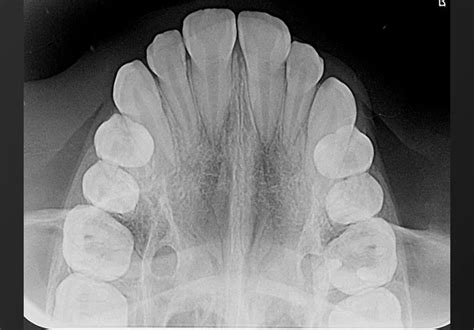

Figura 7A Vista oclusal de modelos pretratamiento.

Modelo superior Observamos una forma de arcada parabólica, con maxilar comprimido, incisivos superiores diastemados y mesiolinguorrotación de ambos primeros molares superiores (fig. 7A).

Modelo inferior La arcada describe una curva catenaria, con falta de espacio en la región de incisivos inferiores, que se encuentran apiñados. La discrepancia oseodentaria inferior, estimada en función del percentil 75 de las tablas de Moyers, es de -6,6 mm (fig. 7A).

Modelos en máxima intercuspidación Existe una relación molar de Clase II bilateral, siendo completa en el lado derecho e incompleta en el lado izquierdo. La línea media inferior se desvía 1,5 mm hacia la derecha con respecto a la línea media superior. El resalte está aumentado, siendo de +11 mm. Podemos calificar la sobremordida como completa o de 3/3 (fig. 7B).